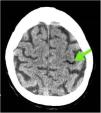

This is the case of a hospitalized patient whose jugular central catheter is removed while sitting on a couch prior to his hospitalization. A few seconds later, the patient develops dissociative disorder, hypokinesia, and acute respiratory failure. A stroke is suspected. The simple cranial CT scan and coronary computed tomography angiography (CCTA) performed reveal no signs of acute ischemia or major cerebral vessel occlusion, but the presence of numerous aerial bubbles at right jugular vein, cerebral cavernous sinuses, extra-axial intracranial sinuses, and a few intra-medulla oblongata bubbles at clivus level (Figs. 1–3). All signs of venous air embolism. This is a rare complication associated with central venous catheters. However, proper management of these is important regarding insertion, maintenance, and removal both at the intensive care unit and hospital ward settings to avoid complications.